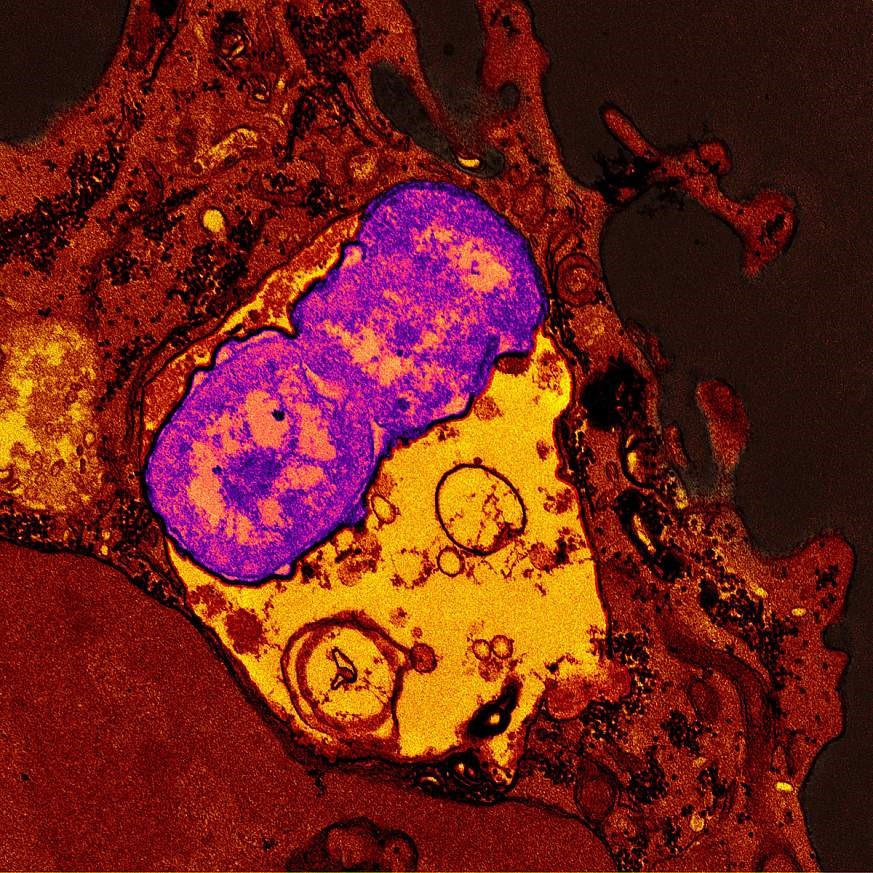

A human neutrophil (red) containing ingested Klebsiella pneumonia (purple)

Now, the same NIAID research group at Rocky Mountain Laboratories in Hamilton, Montana, is investigating similar questions about the new Klebsiella strains, such as whether the microbes can evade human immune system defenses. Their findings were unexpected: the hvKp strains were more likely to survive in blood and serum than MDR hvKp strains. And neutrophils had ingested less than 5% of the hvKp strains, but more than 67% of the MDR hvKp strains—most of which were killed.